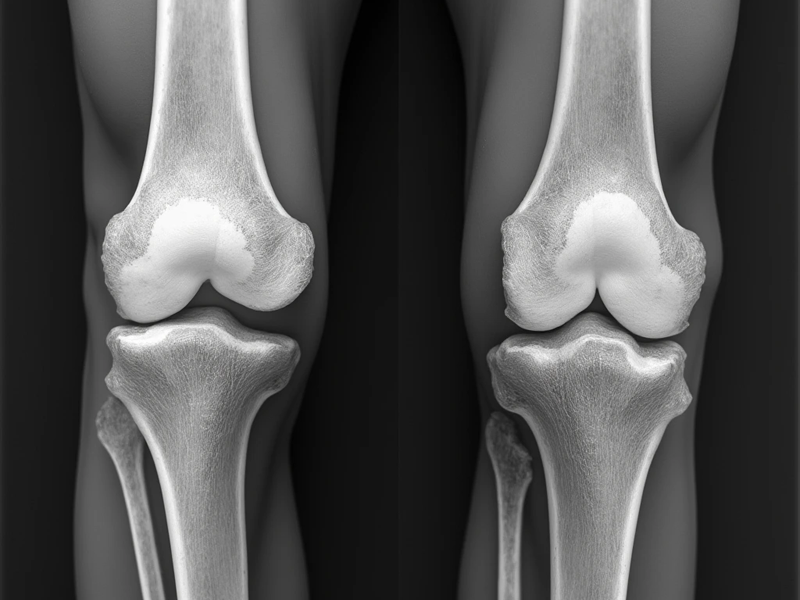

عوارض احتمالی جراحی تعویض مفصل زانو، همانند هر جراحی دیگری میتواند بعد از جراحی گریبان گیر افراد شود. عوارضی که در اکثر افرادی که تعویض مفصل زانو انجام دادهاند دیده میشود سفتی زانوها است. تعویض مفصل زانو که به آن آرتوپلاستی هم گفته میشود میزان موفقیت بالایی دارد. مشکلات و عوارض تعویض مفصل زانو در […]

جراحی مجدد تعویض مفصل زانو، به دلیل بروز مشکلاتی در عملکرد پروتز حاصل میشود. با وجود اینکه پروتزهایی که در زمان جراحی تعویض مفصل زانو، استفاده میشوند به نحوی طراحی شدند که ماندگاری چند ساله داشته باشند، اما در برخی مواقع امکان دارد پروتز دچار مشکل شود و نیاز باشد که پروتز را تعویض کرد. […]